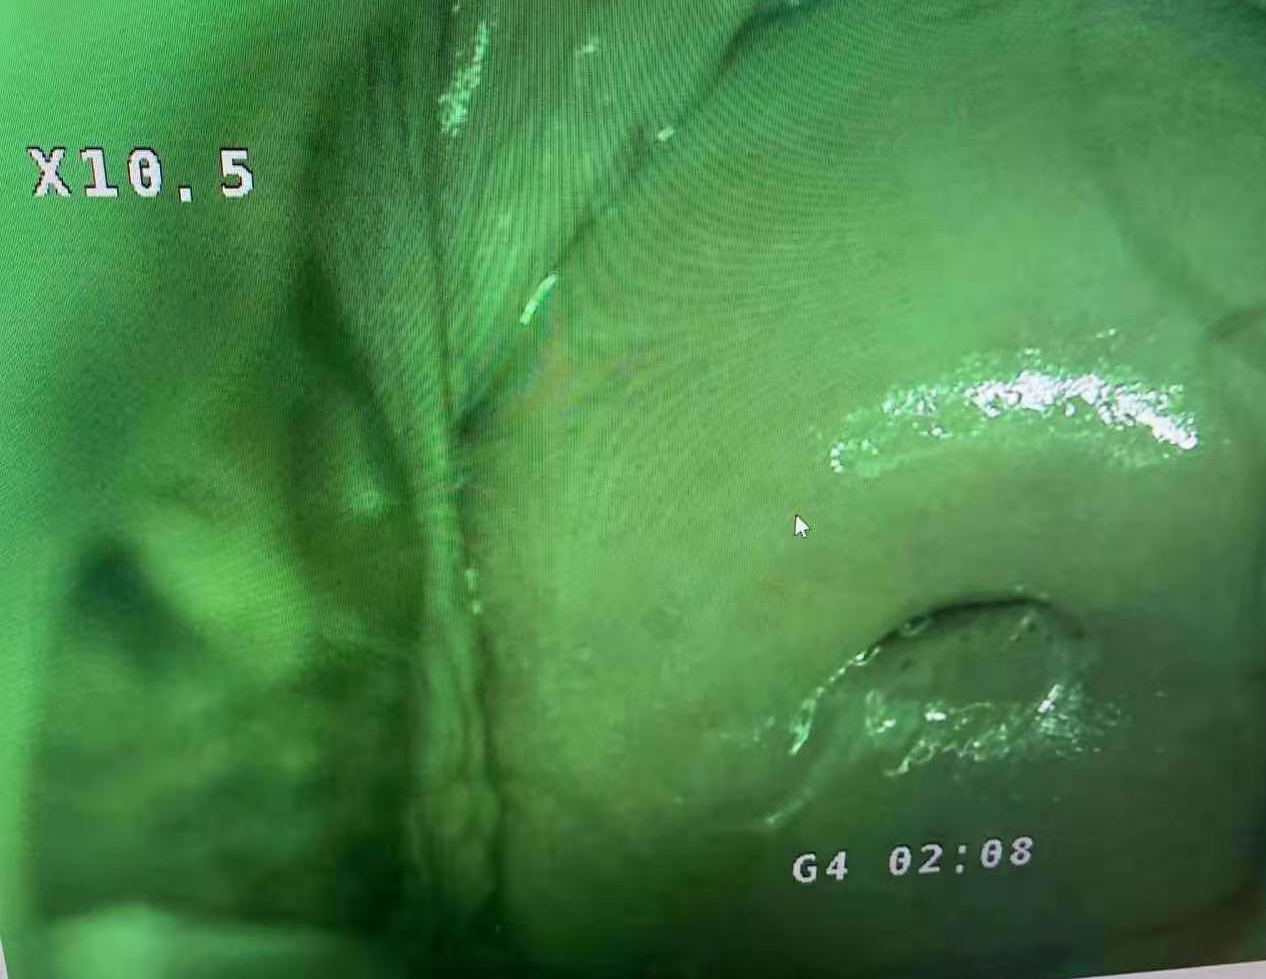

**Extra long depth of field, super large field of view, super three-dimensional sense, realistic color reproduction, unique light path design, providing true 3D visual effects for pre-cancerous, pre-lesional punctiform vessels, columnar epithelium and some tiny lesions .

**50times System Magnification ,17 times optical amplication,3 times Digital amplification.able to output divine clear view of the examination lesion parts. Provide doctors with 3D visual image of the epithelial tissues,and different levels of the blood vessels. **LED light source,lifespan more than 20,000hours. **Horizontal Resolution up to 2064.

Real cervical diagnosis pictures